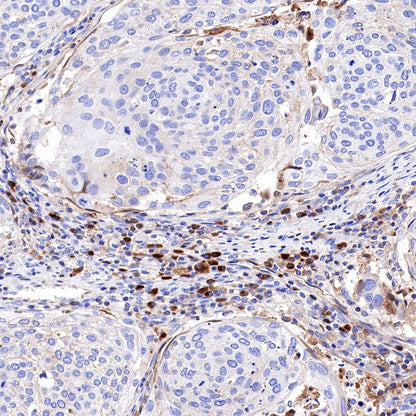

IHC shows positive staining in paraffin-embedded human tonsil. Anti-Kappa light chain antibody was used at 1/500 dilution, followed by a HRP Polymer for Mouse & Rabbit IgG (ready to use). Counterstained with hematoxylin. Heat mediated antigen retrieval with Tris/EDTA buffer pH9.0 was performed before commencing with IHC staining protocol.

IHC shows positive staining in paraffin-embedded human spleen. Anti-Kappa light chain antibody was used at 1/500 dilution, followed by a HRP Polymer for Mouse & Rabbit IgG (ready to use). Counterstained with hematoxylin. Heat mediated antigen retrieval with Tris/EDTA buffer pH9.0 was performed before commencing with IHC staining protocol.

IHC shows positive staining in paraffin-embedded human colon. Anti-Kappa light chain antibody was used at 1/500 dilution, followed by a HRP Polymer for Mouse & Rabbit IgG (ready to use). Counterstained with hematoxylin. Heat mediated antigen retrieval with Tris/EDTA buffer pH9.0 was performed before commencing with IHC staining protocol.

IHC shows positive staining in paraffin-embedded human cervical squamous cell carcinoma. Anti-Kappa light chain antibody was used at 1/500 dilution, followed by a HRP Polymer for Mouse & Rabbit IgG (ready to use). Counterstained with hematoxylin. Heat mediated antigen retrieval with Tris/EDTA buffer pH9.0 was performed before commencing with IHC staining protocol.

IHC shows positive staining in paraffin-embedded human thyroid cancer. Anti-Kappa light chain antibody was used at 1/500 dilution, followed by a HRP Polymer for Mouse & Rabbit IgG (ready to use). Counterstained with hematoxylin. Heat mediated antigen retrieval with Tris/EDTA buffer pH9.0 was performed before commencing with IHC staining protocol.